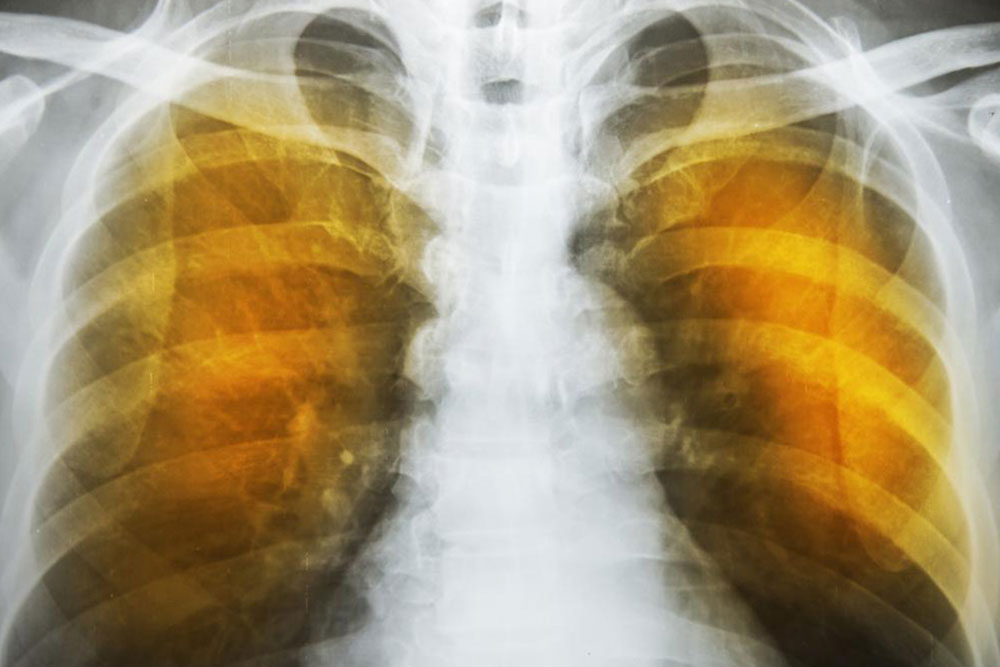

The symptoms of emphysema are exceedingly severe and cause considerable damage to the lungs before the symptoms even show up. Generally, one feels a lack of energy and the tendency to skip some of the common daily routines.

As the deterioration continues, the alveoli lose their strength and start rupturing. In extreme cases, there may be large scale destruction which leads to empty spaces in lungs called bullae. This would reduce the functional area of the lung which in extreme cases call for surgical removal. In an extremely rare condition, large scale rupture of alveoli can cause a condition called pneumothorax and the collapse of the lung, a very serious condition, which can be fatal. The best thing one can do is stop exposure to irritants.